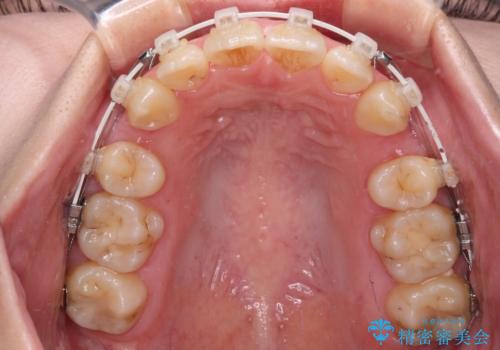

- 前歯のデコボコと突出感を気にして来院された患者様です。

上下左右第一小臼歯4本を抜歯して、積極的に口元を引っ込めるよう、ワイヤー装置にて矯正治療を行うこととしました。